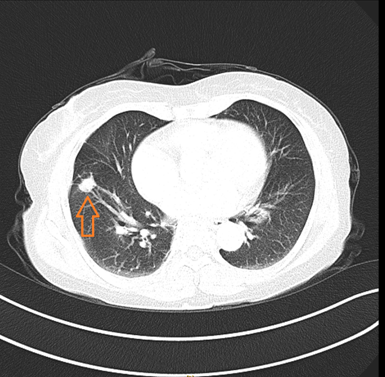

家住阆中的涂阿姨最近经常发生眩晕,为了解决眩晕的问题来到我院神经内科就诊,经过CT检查发现右肺下叶有一个直径约1.5厘米结节,经病理活检后考虑为“肺腺癌”。经胸外科会诊后认为“肺腺癌”诊断明确,且无手术禁忌,建议转到胸外科做胸腔镜手术将肿瘤切除。